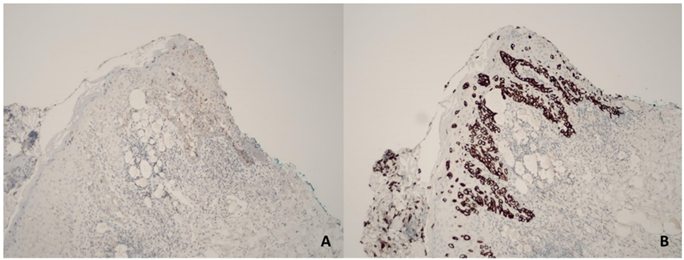

Immunohistochemistry showed positivity for CK7 and HER2 (2+), negativity for hormonal receptors and melanocytic markers, a profile consistent with Paget’s disease of the breast (Figure 3).

Figure 3: Immunohistochemistry: A) HER-2 positive (2+). B) CK7 positive.

The presence of intraepidermal Paget cells with clear cytoplasm and pleomorphic nuclei is the characteristic histopathological finding. Immunohistochemistry is essential to differentiate PDB from other pagetoid entities such as malignant melanoma or squamous cell carcinoma in situ. Markers such as CK7, EMA, CEA, GCDFP-15, and HER2 are typically positive in Paget cells [7].